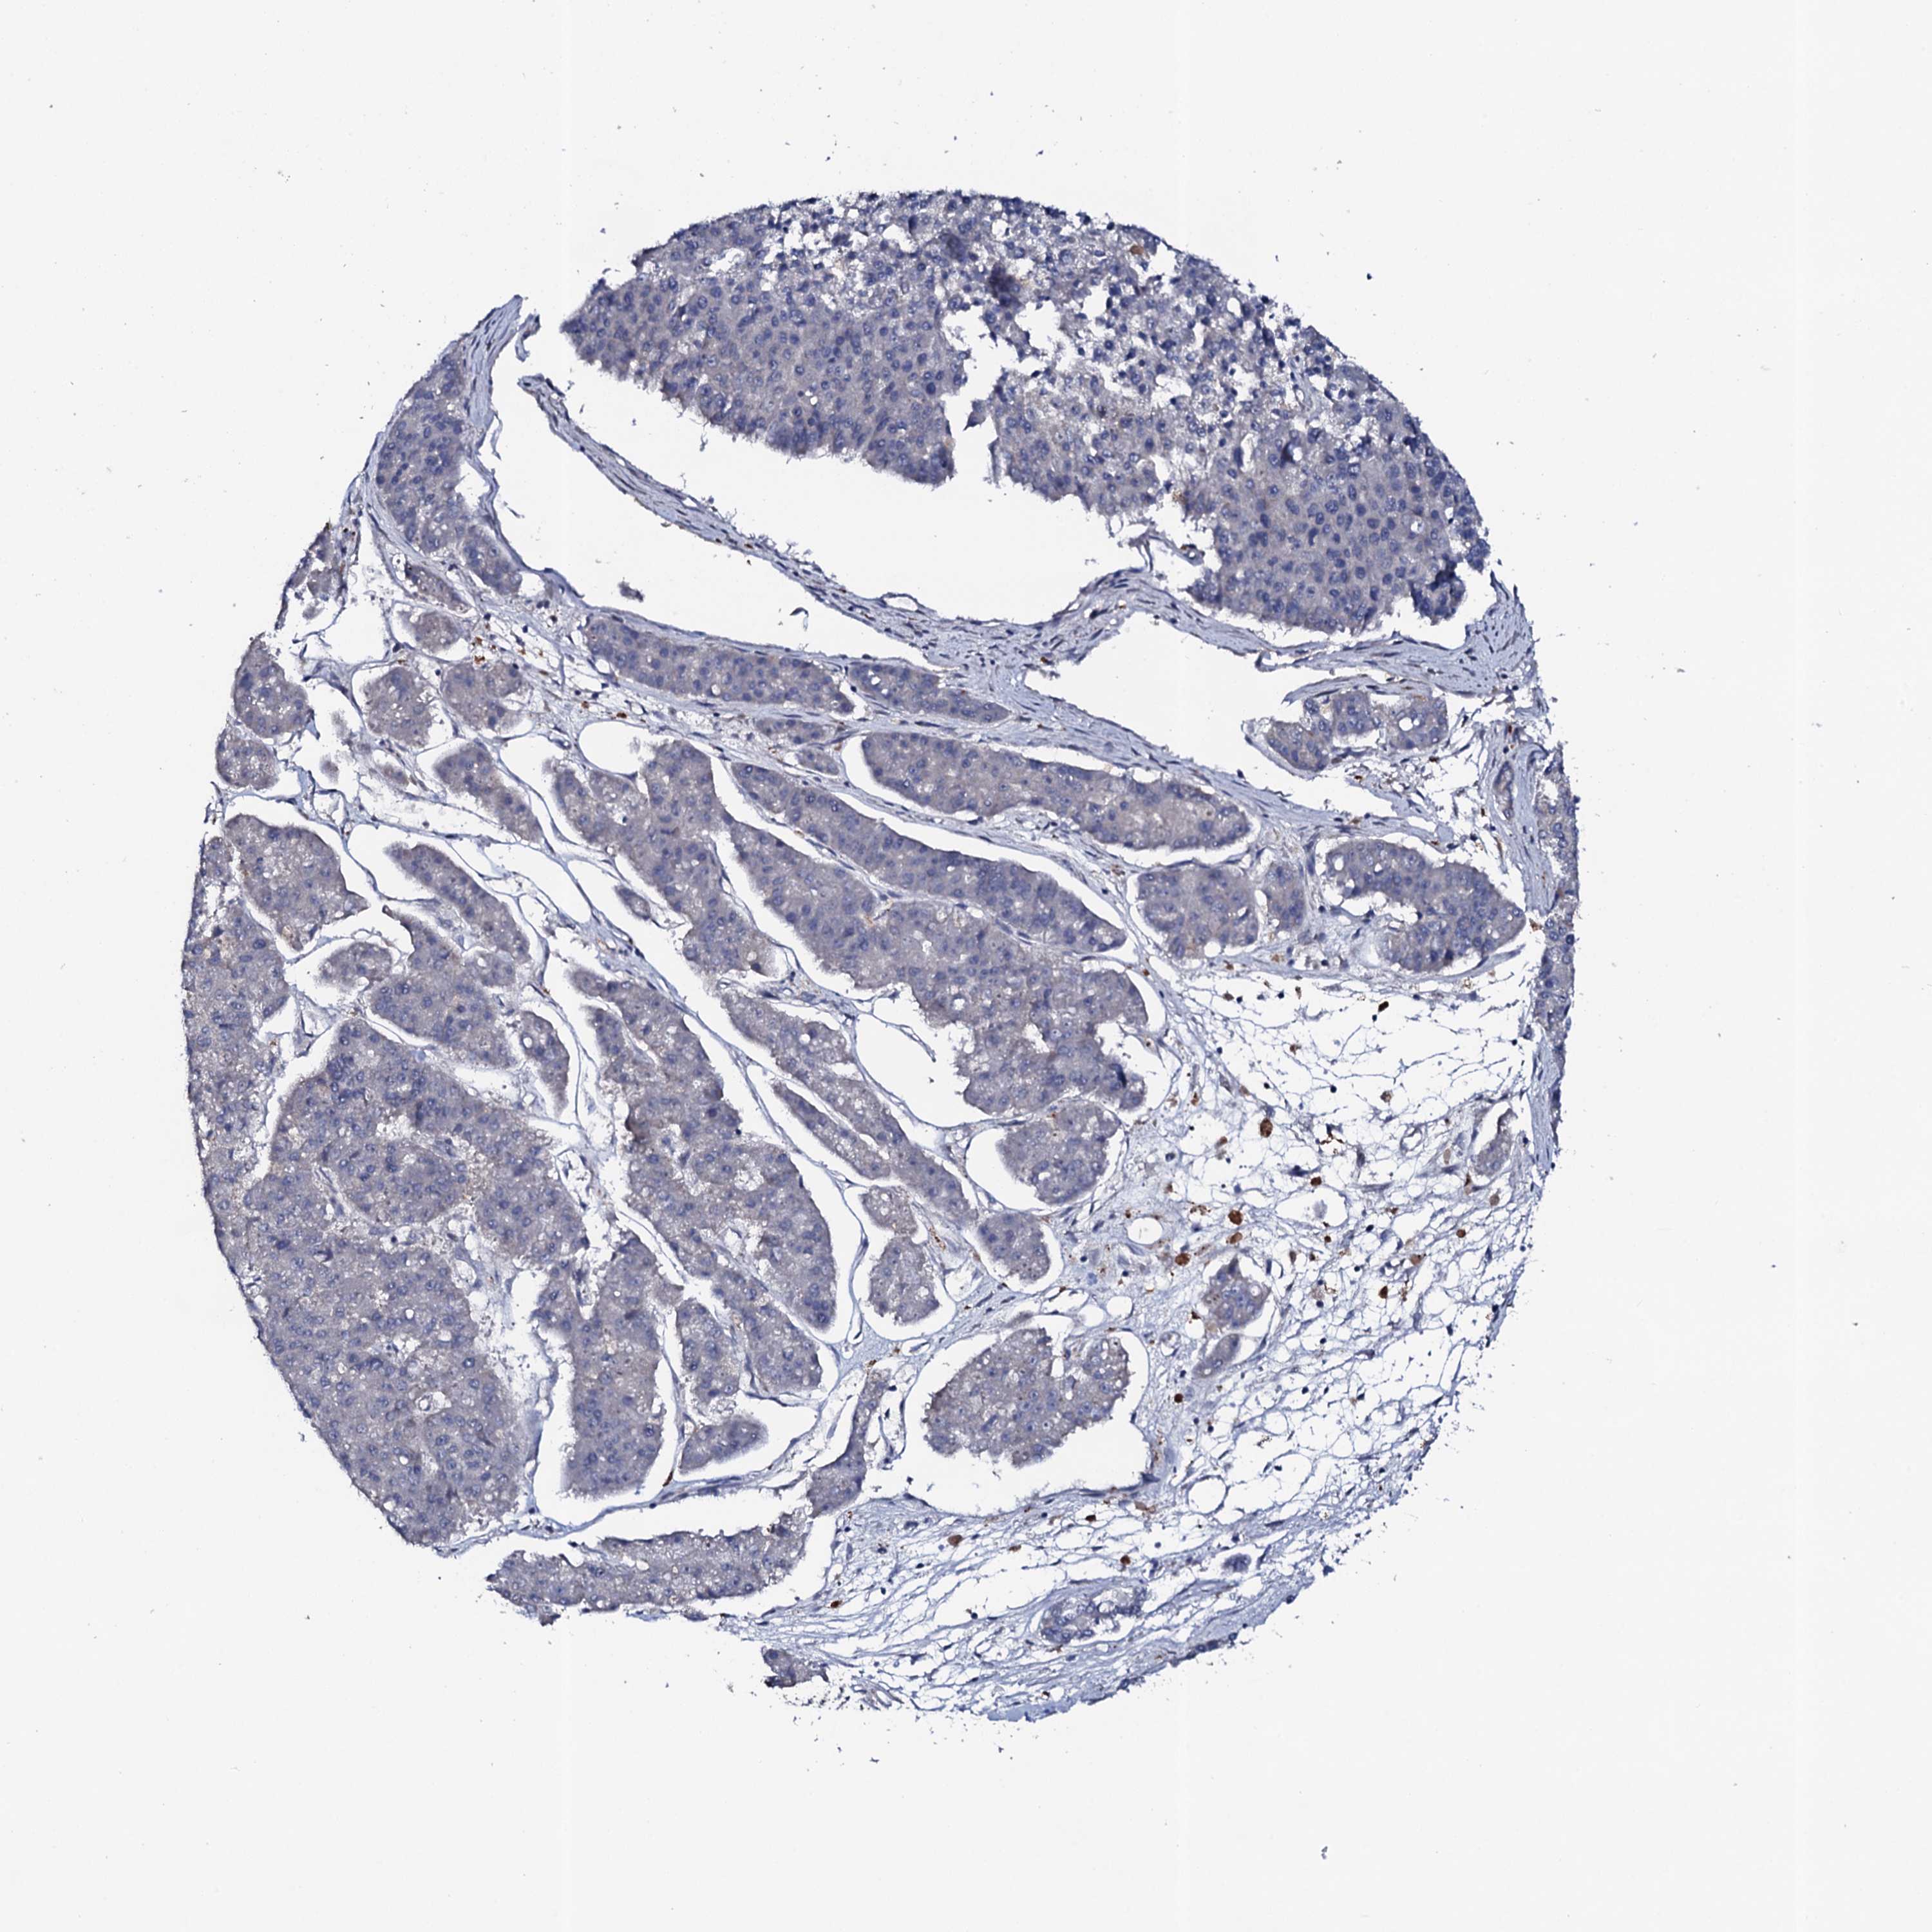

PANCREATIC CANCER - Protein expressioni

A mouse-over function shows sample information and annotation data. Click on an image to view it in a full screen mode. Samples can be filtered based on level of antibody staining by selecting one or several of the following categories: high, medium, low and not detected. The assay and annotation is described here.

Note that samples used for immunohistochemistry by the Human Protein Atlas do not correspond to samples in the TCGA dataset.

Antibody stainingi

Antibody staining in the annotated cell types in the current human tissue is reported as not detected, low, medium, or high, based on conventional immunohistochemistry profiling in selected tissues. This score is based on the combination of the staining intensity and fraction of stained cells.

Each image is clickable and will lead to virtual microscopy that enables deeper exploration of all samples and also displays staining intensity scores, fraction scores and subcellular localization as well as patient and tissue information for each sample.

Antibody HPA040459

Staining

High

Medium

Low

Not detected

Intensity

Strong

Moderate

Weak

Negative

Quantity

>75%

75%-25%

<25%

None

Location

Nuclear

Cytoplasmic/membranous

Cytoplasmic/membranous,nuclear

Adenocarcinoma, NOS